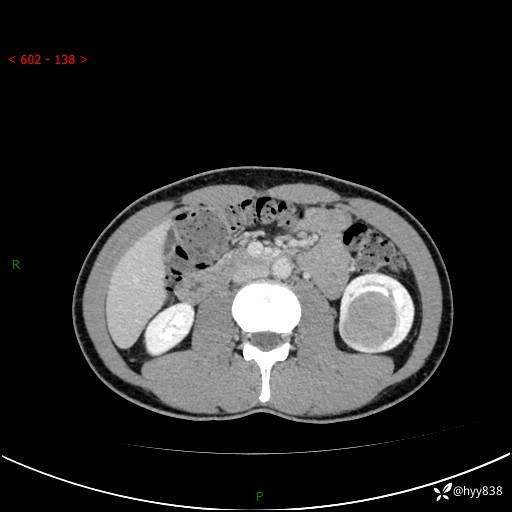

年轻男性,发现左肾占位1天。“非好病例”我不发,误诊率高---(有结果)

现病史:患者昨日中午进食后出现明显腹痛,腹泻,在我院急诊科行补液及对症治疗,双肾输尿管彩超提示左肾占位(5.2*4.3cm),平素无明显腰痛,无再发肉眼血尿等情况,现为求处理左肾占位,遂来我院,门诊以左肾占位收治入院。 患者起病以来,精神、食欲、睡眠尚可,大便可,小便如上,体力体重无明显下降。

双肾CT平扫+增强(三期)